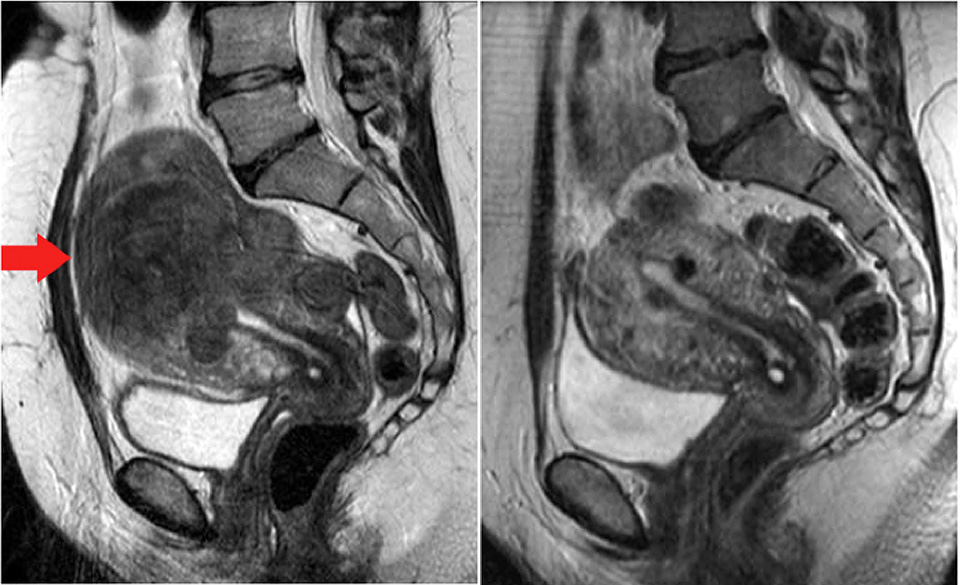

Uterus submucous myome is indication for surgery treatment.

Le myome est un type de tumeurs mésenchymales. Myome sind gutartige geschwulste in der gebärmutter. Uterus submucous myome is indication for surgery treatment. Myome entstehen aus muskelzellen der gebärmutter. Diese wachsen schneller, als umliegende muskelzellen.